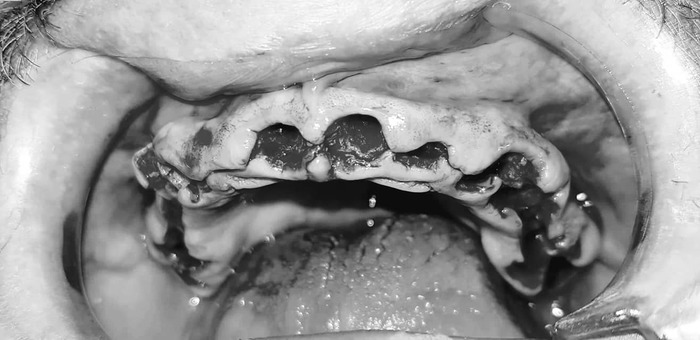

Итак - панорама до:

Как бы уже понятно, что хорошего мало, но к такому я шел примерно лет 20 своей жизни и как-то привык.

Теперь - как это все дело выглядело в реале:

Вот честно, пока я не увидел именно эти две фотки - я слабо осознавал, какой именно у меня пипец во рту. Каждое утро в зеркале это воспринималось немного не так. Передергивало, конечно, но было привычно. Кстати, все эти фото я увидел уже сильно после лечения и никакого влияния на мое решение лечиться у Георгия они не оказали - не успели )))